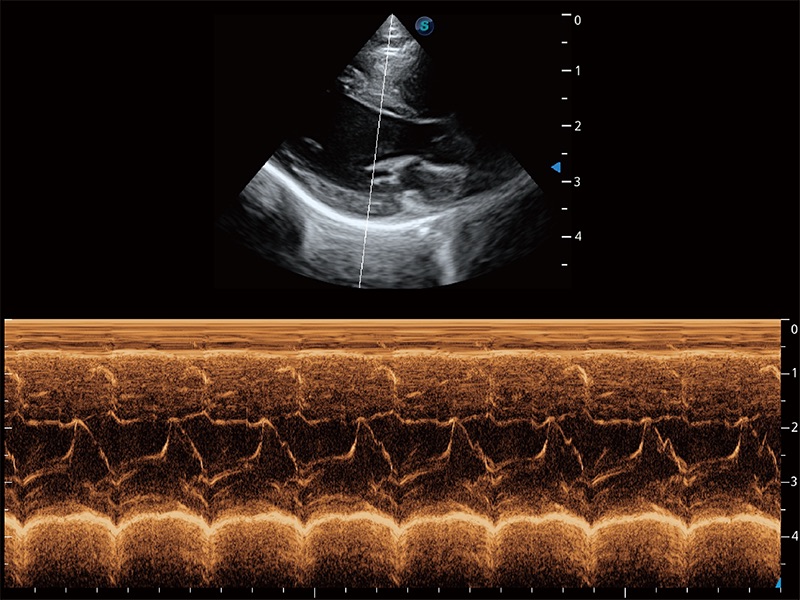

ProPet 80 配備了豐富的心臟探頭群、先進的成像技術(shù)和專業(yè)的心臟測量工具,可幫助動物醫(yī)生為不同體型和生理結(jié)構(gòu)的動物提供心臟和心肌功能的全面評估。

實時用顏色表示心肌組織運動,觀察和定量組織的運動情況,對快速檢測與評估心肌的灌注和活性、電傳導及心肌收縮和舒張功能等均能提供重要的診斷信息。

通過360度任意調(diào)節(jié)3條M型取樣線,在同一心動周期上觀察心臟不同位置的運動曲線,得到準確的心功能測量數(shù)據(jù),有效評估心肌運動及左心室功能。

能夠基于左心室壁追蹤和辛普森法,自動計算射血分數(shù),支持多個可移動點描跡,與手動測量相比,極大節(jié)省了動物醫(yī)生的時間和精力。